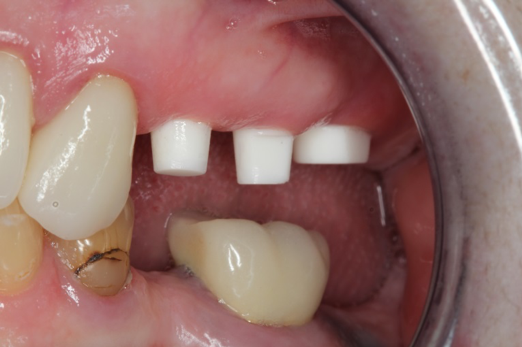

Fig 15. Provisionals 12 weeks postoperatively.

Figure 15

After the preparations were evaluated and accepted by the clinician, provisionals were completed with traditional crown-and-bridge techniques. Then the provisionals were fabricated with a replication stent derived from the diagnostic wax up (Figure 14). The provisionals were well-fitted to both the natural dentition and the ceramic dental implants (Figure 15). The provisional that was fixed to the implant was kept out of occlusion and had a narrow buccal-lingual occlusal table. The smaller occlusal table and short occlusal scheme provided light loading forces and stimulated the bone tissuethe brain detects the stimuli and sends osteoblasts to the area to increase bone density surrounding the implant. The recommendation for the light-loading provisional phase was to have the patient function with the provisionals for 4 weeks.